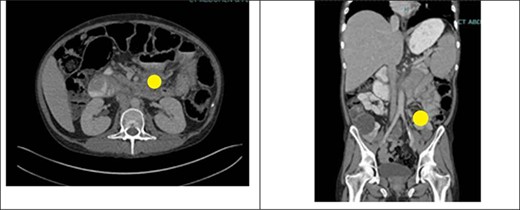

Prior to the index presentation, the patient presented to the emergency department with generalized weakness and blood per rectum for 2 weeks. He had no changes in diet, but endorsed intermittent abdominal discomfort, as well as increasing anal pain and drainage. The only abnormality on digital rectal examination was minor peri-rectal excoriation. Computed tomography CT imaging (Fig. 1) shows significant ascites, a non-obstructing mass at the base of the mesentery rectum, mesenteric adenopathy and dilated loops of small bowel. There were no signs of obstruction or abdominal distension. Evaluation under anesthesia demonstrated a large, firm indurated necrotic mass above the dentate line forming a malignant fistula to the perianal skin. There was also thickening of the perianal skin circumferentially that was likely secondary to chronic irritation from fistulous drainage or pagetoid spread of a malignancy. Biopsy results revealed poorly differentiated invasive squamous cell carcinoma with extensive necrosis. Left and right lateral perianal skin showed focal severe squamous dysplasia and high-grade squamous dysplasia, respectively. Ultimately, the diagnosis of stage T3N0M0 squamous cell carcinoma of the anus was made.

CT abdomen and pelvis with IV contrast showing an ill-defined mass at the root of the mesentery measuring at least 5.2 × 5.1 cm (yellow circle). This was hypothesized to represent conglomerate lymphadenopathy, a potential neoplasm, such as mesothelioma or lymphoma, or metastatic disease. There was also a large volume of abdominal ascites and mildly dilated loops of small bowel within the left abdomen which likely represented a partial obstruction or ileus.